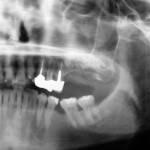

Riabilitazione chirurgica e implanto-protesica in esiti di frattura mandibolare – Caso clinico

Riassunto

Gli autori descrivono un caso clinico di grave malocclusione a seguito di trauma mandibolare trattato in altra sede. Il piano di trattamento ha previsto...